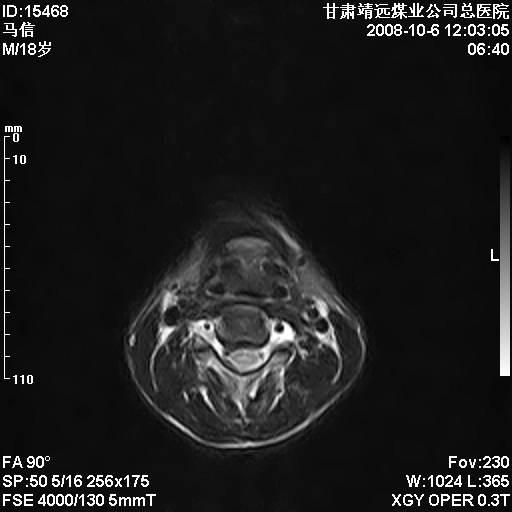

患者18岁,学生,在玩耍中受伤来检查,患者喜欢打篮球。颈椎内异常信号影,我们考虑占位,但是不像占位,又考虑硬膜囊的增厚,大家关建看颈椎椎管内的那个异常占位信号

腰椎的改变是不是正常发育的改变,还是打篮球的长期慢性损伤。

后纵韧带增厚,颈2/3、3/4、4/5、5/6椎间盘变性、突出;椎体有旋转,提示椎小关节有问题;腰椎间盘变性,许莫氏结节。

后纵韧带增厚,颈2/3、3/4、4/5、5/6椎间盘变性、突出;椎体有旋转,提示椎小关节有问题。腰椎诸椎体终板骨骺炎可能性大!支持!